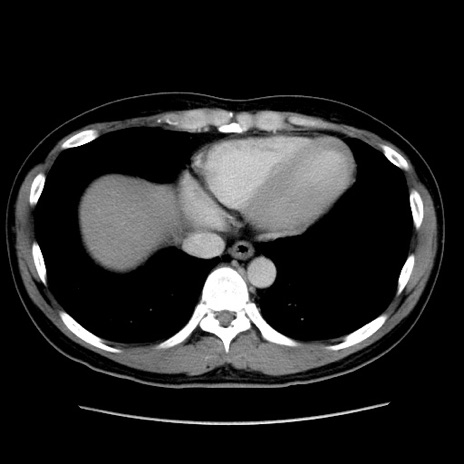

症例4(横断像)

【症例】30歳代男性

【主訴】腹痛、嘔吐

【現病歴】昨晩から突然の腹痛あり、その後嘔吐、軟便も出現。腹痛が改善しないため救急搬送となる。2日前にしめ鯖の食事歴あり。

【身体所見】意識清明、苦悶様、BP 135/90mmHg、BT 35.7℃、腹部:平坦、やや硬、心窩部〜臍部に自発痛、圧痛あり、筋性防御+、反跳痛-

【データ】WBC 8100、CRP 0.57